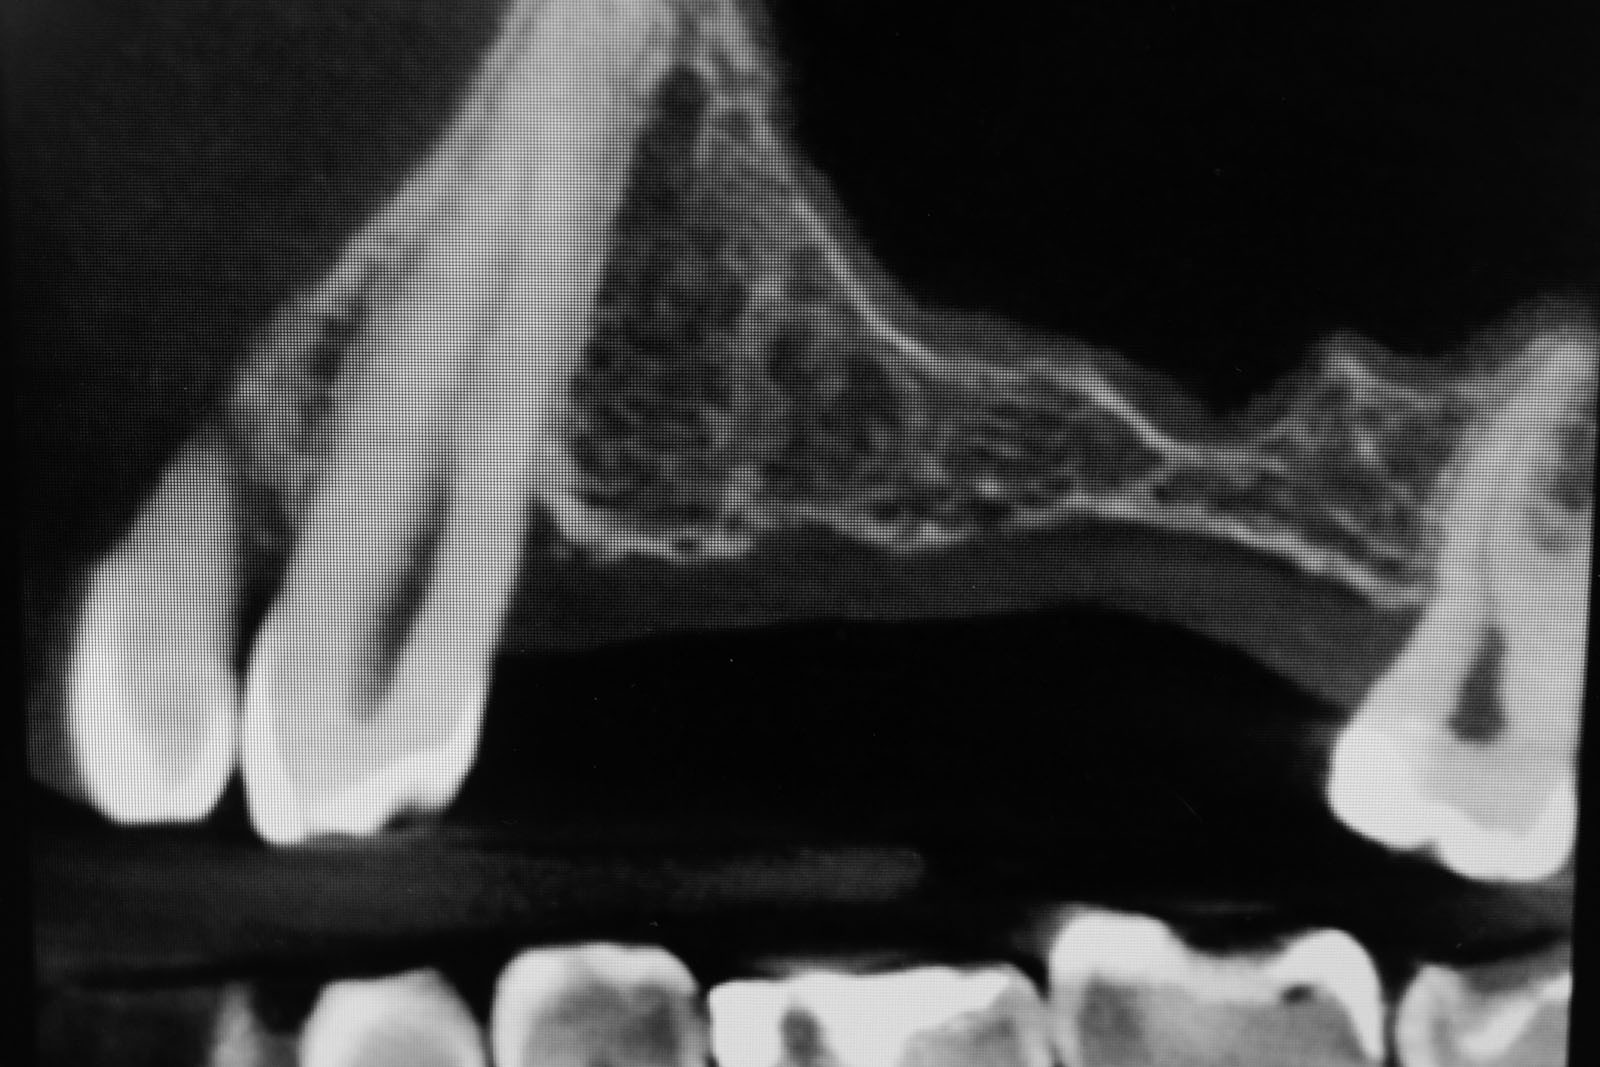

Zabiegiem, który rozwiązuje ten problem, jest podniesienie dna zatoki szczękowej, czyli odbudowa kostna w okolicy zębów trzonowych. Ubytek kości uzupełniany jest materiałem kościotwórczym, który układany jest pod błoną wyścielającą zatokę szczękową, zwaną membraną Schneidera. Zmniejszając objętość zatoki szczękowej, tworzy się tym samym stabilną strukturę kostną, umożliwiającą zabieg implantacji wszczepów śródkostnych.

Zatoki szczękowe to symetrycznie umieszczone w kościach szczęk przestrzenie powietrzne, posiadające komunikację z jamą nosa. Średnio pojemność zatok wynosi 24 cm3, a ściany wyścielone są błoną śluzową (membrana Schneidera). Dno zatoki szczękowej stanowi wyrostek zębodołowy, w którym umieszczone są zęby, często zlokalizowane tuż pod cienką wyściółką zatoki. Statystycznie najwęższy obszar kostny w tej strefie zlokalizowany jest na wysokości zębodołów pierwszego i drugiego zęba trzonowego.

• Metoda otwarta – opisana w 1980 przez Jamesa i Boyna – polega na chirurgicznym dostępie do zatoki szczękowej poprzez jej boczną ścianę, następnie delikatnej preparacji, oddzieleniu wyściółki (błony Schneidera) bez jej perforacji, umieszczeniu pomiędzy nią a dnem zatoki materiału odbudowującego kość. Zabieg podniesienia dna zatoki szczękowej może przebiegać z jednoczesnym wszczepieniem implantów lub wszczepieniem ich w czasie odroczonym o 6–8 miesięcy. Warunkiem jednoczesnego wszczepienia implantów jest możliwość pierwotnie stabilnego ich umocowania w pozostałej własnej kości wyrostka zębodołowego. Najmniejsza jej ilość wg niektórych autorów to 1 mm.